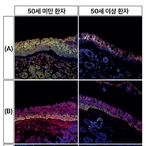

고려대 구로병원 "외상 환자, REBOA 안전하게 적용하려면 ..연령별로 다른 맞춤형 접근 필요"

- 2026-04-07 09:18

- 노재영 기자